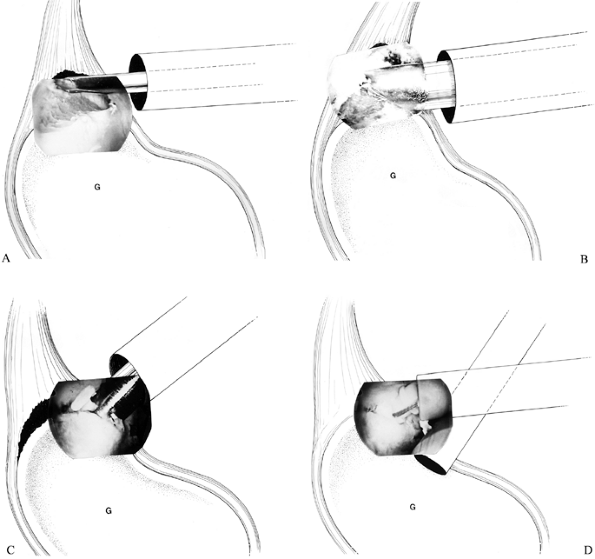

The standard posterior, anterosuperior, and anteroinferior portals as

Figure 80.34. Arthroscopic repair of a SLAP lesion using a transglenoid suture technique. A: Prepare the glenoid rim. B: Drill transglenoidally with a Beath needle. C:

Pass the suture that is subsequently tied over the infraspinatus

fascia. (From Altchek DW, Warren RF, Skyhar MJ. Shoulder Arthroscopy.

In: Rockwood CA Jr, Matsen FA III, eds. The Shoulder. Philadelphia: WB Saunders, 1990:275, with permission.)